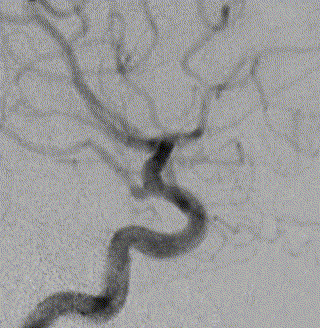

右侧颈动脉造影

左侧颈动脉造影

左侧颈内动脉重建(左侧狭窄及扩张较右侧更甚)

术前                         术后3个月